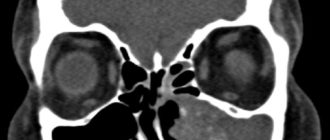

Мицетома верхнечелюстной пазухи

Гайморова пазуха и «грибковое тело» Чаще всего речь идет о мицетоме или воспалении грибкового